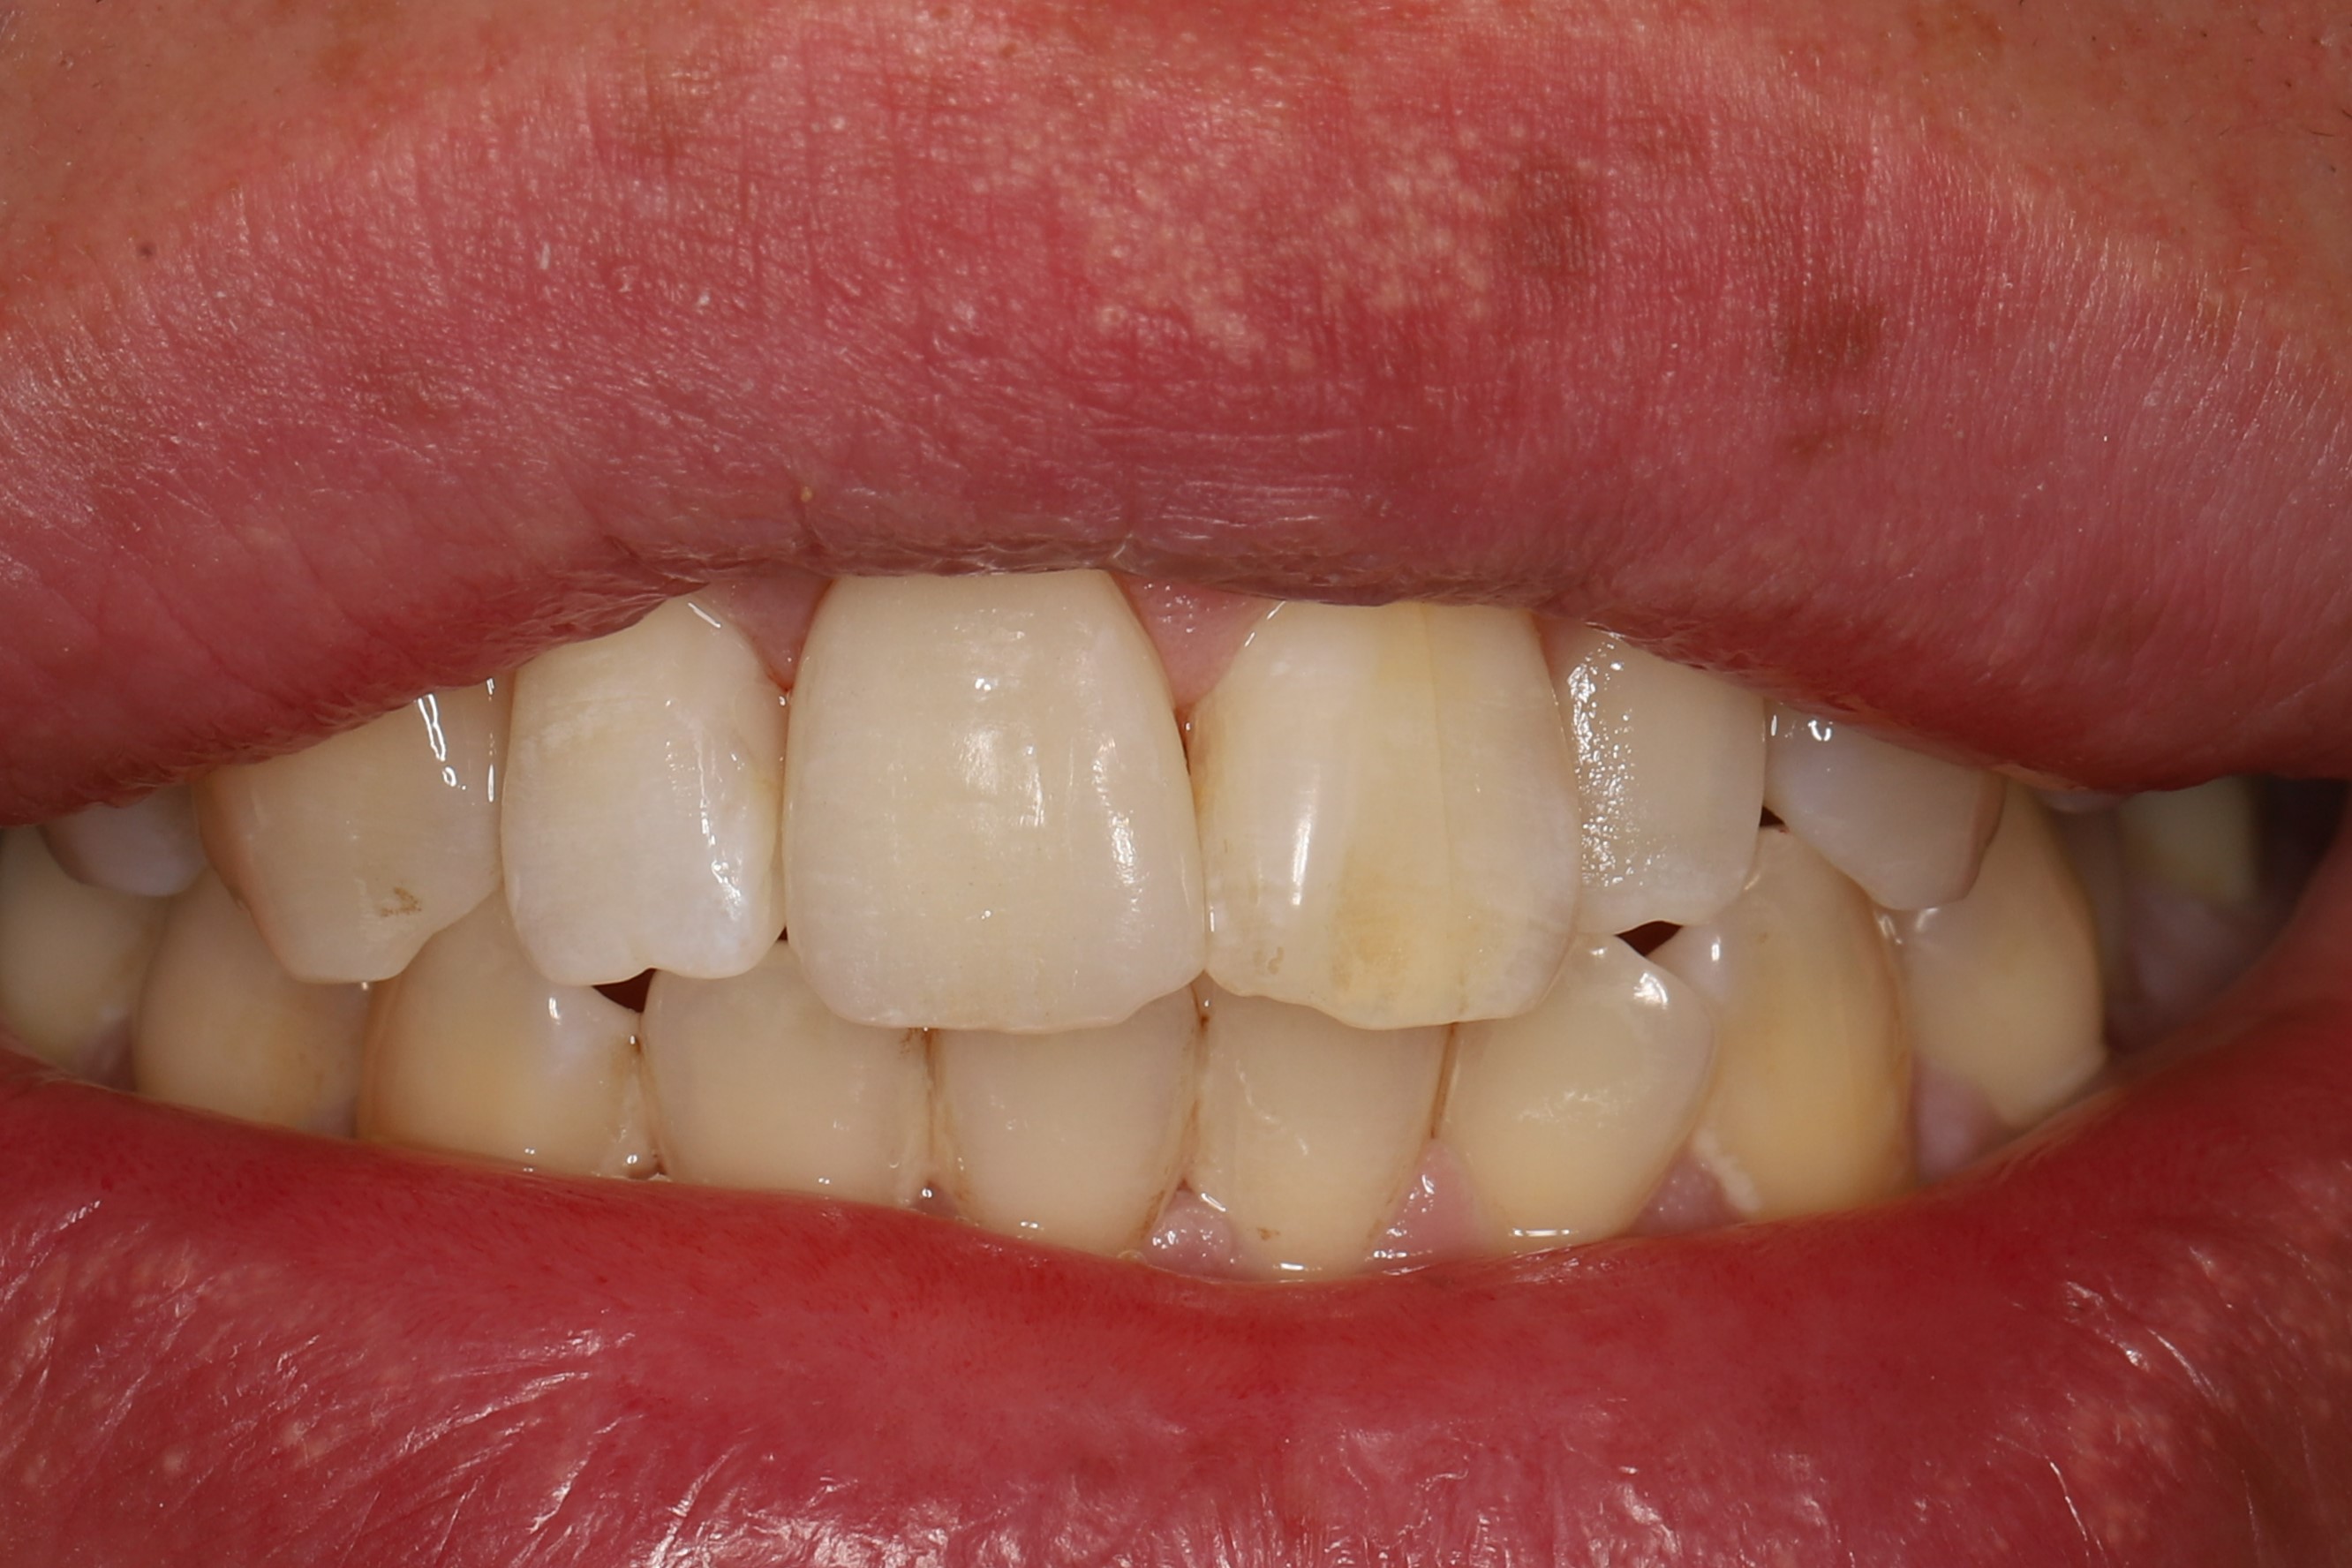

症例2(歯の色+形に問題がある場合)

治療前

ホワイトニング後(治療期間2ヶ月)

虫歯を除去し、最小限の切削量で被せ物により歯の形を改善後